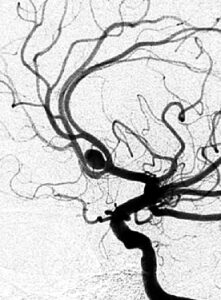

足の付け根からカテーテルを血管内に挿入し、レントゲンと造影剤を使って透視しながら動脈瘤内に進めます。そして柔軟なプラチナ製のコイルを動脈瘤内に充填します。コイルが動脈瘤から血管に逸脱する場合には、風船のついたカテーテルで一時的に支えたり、ステントを併用することもあります。治療後はカテーテルを抜去し、穿刺部を止血して、麻酔をさまして専用病棟へ帰室します。